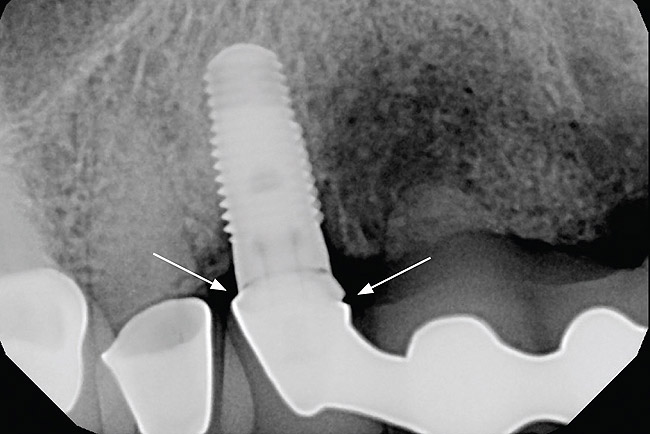

The patient returned regularly for recall visits for 7 years, but then did not return for follow-up or maintenance for 2 years. He then returned for evaluation and retreatment of the implant. However, retreatment was not possible as the bone loss and lesion morphology were unfavorable for attempting a regenerative approach (Figure 14). The implant was removed atraumatically, and the site was grafted with a composite graft of mineralized and demineralized freeze-dried bone allograft and covered with an absorbable porcine collagen barrier. The flap was advanced to enable primary closure of the site and it was allowed to heal for 6 months. Re-entering the site, the bone fill achieved by the regenerative efforts enabled a second implant to be placed in a favorable prosthetic position (Figure 15 and Figure 16).

Figure 14  Recurrence of peri-implant bone loss as a result of 2 years of no maintenance, rendering the implant hopeless.

Figure 14